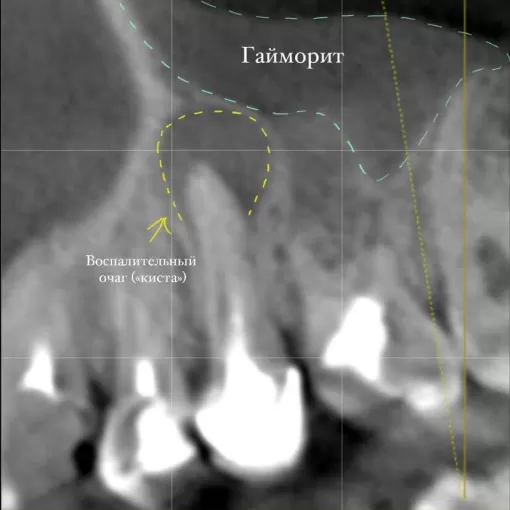

Пациент обратился с целью имплантации в области отсутствующего зуба 4.6. Однако после КЛКТ (3Д) исследования был обнаружен воспалительный процесс (киста) в области соседнего зуба 4.7 (рис. 1).